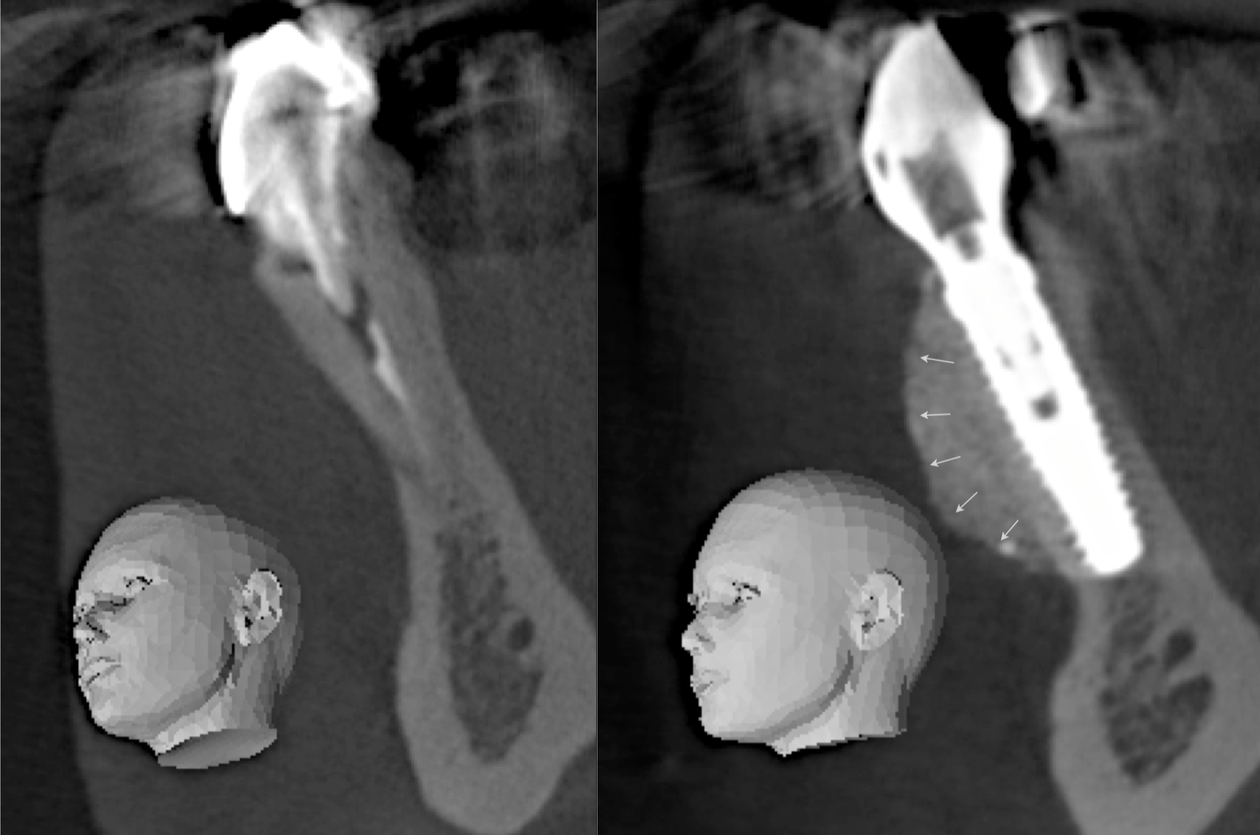

Clinical Cases CASE 1. COMPLEX IATROGENIC DEFECT CASE 2. CONGENITALLY MISSING LATERAL INCISORS CASE 3. VERTICAL AUGMENTATION CASE 4. VERTICAL AUGMENTATION CASE 5. IMPLANT BONE DEHISCENCE CASE 6. IMPLANT BONE DEHISCENCE CASE 7. KNIFE-EDGE RIDGE CASE 8. IMMEDIATE IMPLANT AND SIMULTANEOUS S.M.A.R.T.® HORIZONTAL AUGMENTATION CASE 9. IMMEDIATE IMPLANT AND SIMULTANEOUS S.M.A.R.T.® HORIZONTAL AUGMENTATION